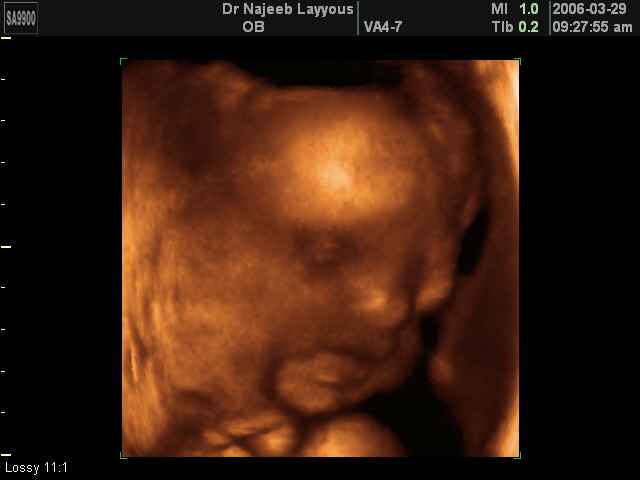

- Fetal Behavior Ultrasound Photos

Ultrasound Photos in 3D showing Fetal Behavior Inside the uterus | Dr N Layyous